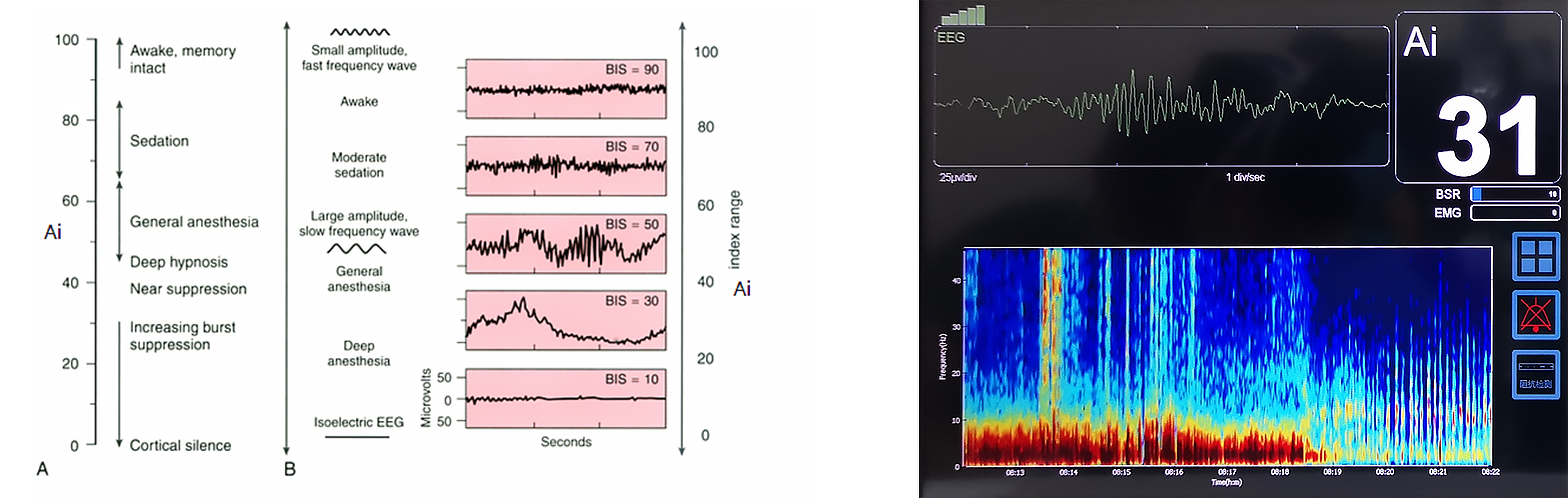

In clinical studies of EEG signaling, profound changes in EEG signals from waking to general anesthesia were accompanied by brain spontaneous electrical activity. The investigator propose to evalsuate the depth of anesthesia with the EEG signal. The important feature is the gradual deepening of anesthesia EEG signal as follows: 1. Disorganized high-frequency signal activity occurs; 2. The frequency and amplitude of EEG signals become more regular, especially in the δ-wave frequency band; 3. The frequency mixing of low-frequency band and high-frequency band occurs, and δ-wave activity occurs under deep anesthesia; 4. The anesthesia deepens, and the burst suppression signal appears. The deeper the anesthesia, the longer the suppression period will be; 5. Equipotential activity will occur at the end.

Therefore, the researchers analyzed various processing methods of EEG signals, and according to the characteristics of EEG signals in the process of anesthesia, finally obtained the quantitative index of evalsuating the depth of anesthesia, so as to quantitatively evalsuate the depth of anesthesia.

Basic principle of Ai anesthesia depth index: Ai anesthesia awareness index is based on multiple indicators such as frequency, double frequency, time domain and complexity.Multivariate statistical methods were used to quantify the brain waves from the awake to the deepest anesthetic state.

Basic principle of Ai anesthesia depth index: Ai anesthesia awareness index is based on multiple indicators such as frequency, double frequency, time domain and complexity.Multivariate statistical methods were used to quantify the brain waves from the awake to the deepest anesthetic state.